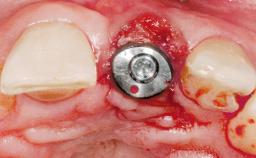

A 36-year-old female patient was referred for the replacement of the upper left central incisor (tooth 21), which had fractured. Although the tooth had been asymptomatic for many years, the crown began to loosen, at which time she presented to her dentist for an assessment. Teeth 21 and 22 had both been endodontically treated many years previously. She was a healthy individual and a non-smoker.

The crown of tooth 21 was splinted to the adjacent teeth with composite resin, and the gingiva was inflamed.